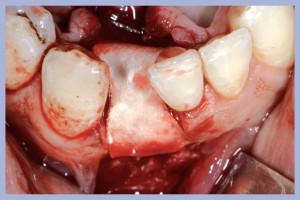

Paziente di sesso maschile di anni 45 in buone condizioni di salute generale presenta una condizione di affollamento in sede 4.1 / 4.2 con compromissione parodontale superficiale e profonda dei siti suddetti (Fig. 1).

- Fig. 1

- Fig. 1a

- Fig. 1b